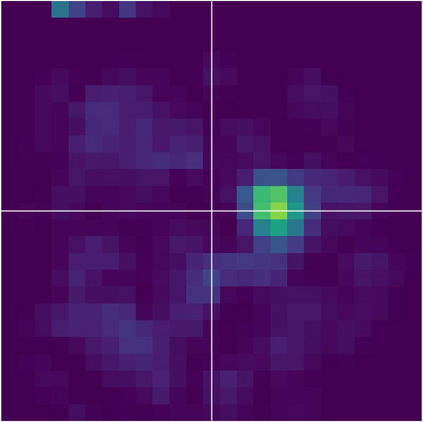

Various imaging modalities allow for time-dependent image reconstructions from measurements where its acquisition also has a time-dependent nature. Magnetic particle imaging (MPI) falls into this class of imaging modalities and it thus also provides a dynamic inverse problem. Without proper consideration of the dynamic behavior, motion artifacts in the reconstruction become an issue. More sophisticated methods need to be developed and applied to the reconstruction of the time-dependent sequences of images. In this context, we investigate the incorporation of motion priors in terms of certain flow-parameter-dependent PDEs in the reconstruction process of time-dependent 3D images in magnetic particle imaging. The present work comprises the method development for a general 3D+time setting for time-dependent linear forward operators, analytical investigation of necessary properties in the MPI forward operator, modeling aspects in dynamic MPI, and extensive numerical experiments on 3D+time imaging including simulated data as well as measurements from a rotation phantom and in-vivo data from a mouse.